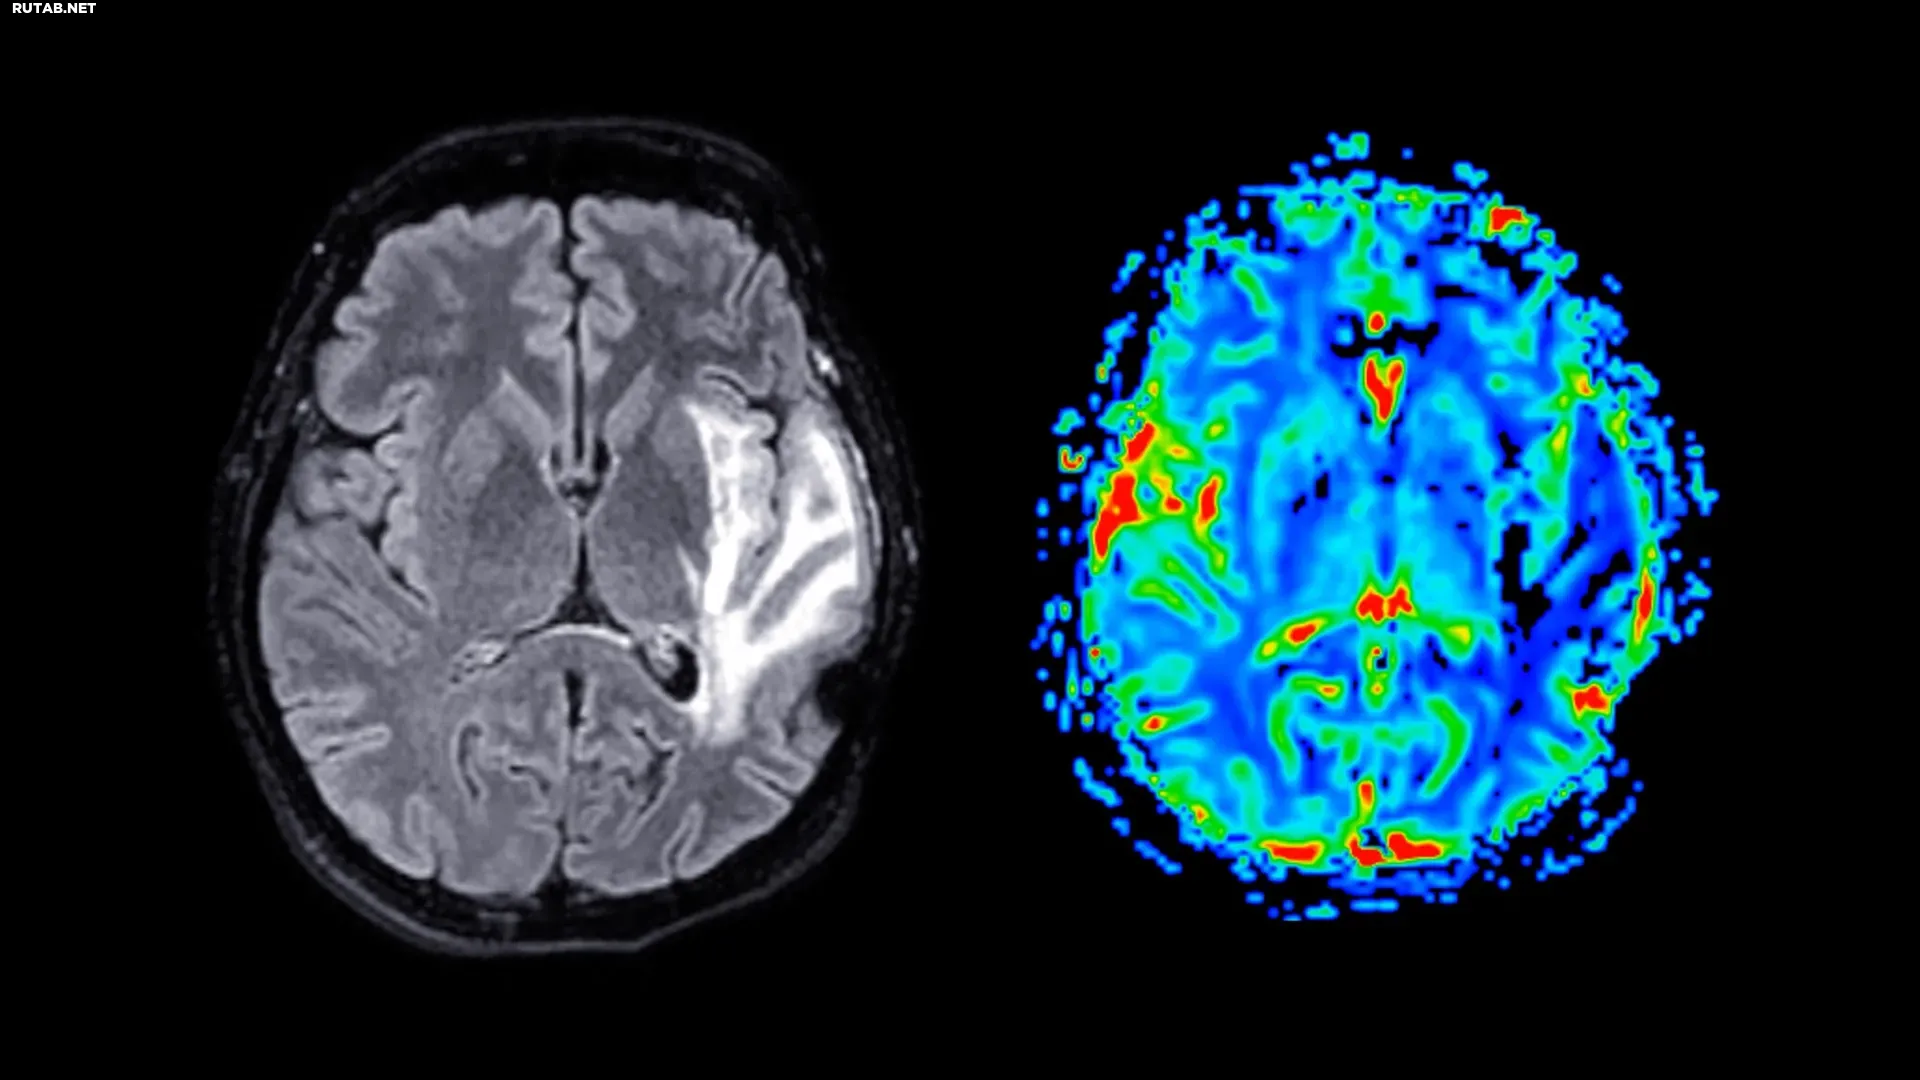

Сканирование мозга выявило значительное сокращение объёма серого вещества у женщин в постменопаузе, независимо от приёма ЗГТ. Наиболее пострадали гиппокамп (отвечает за память), энторинальная кора («шлюз» для передачи информации) и передняя поясная кора (управляет эмоциями и вниманием).

Профессор Барбара Саакян, старший автор исследования, отметила: «Области мозга, где мы увидели эти различия, как правило, страдают при болезни Альцгеймера. Менопауза может сделать этих женщин более уязвимыми в будущем. Это может помочь объяснить, почему случаев деменции среди женщин почти в два раза больше, чем среди мужчин».